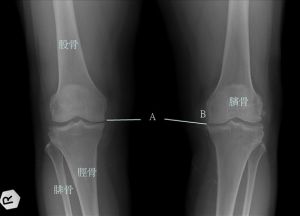

膝蓋--是人體下肢最重要的"負重關節",站立或走平路時膝蓋內軟骨平均要承受1/2—1倍多體重的壓力,上樓梯時增為2倍,下樓梯則增為7倍。因長年承受巨輻壓力的關係,膝蓋關節磨損退化情形年紀愈大愈嚴重。磨損退化的膝關節一旦造成症狀,即稱為退化型膝關節炎。此病非常普遍,年紀愈高愈常見。

退化性關節炎2、膝關節變形:早期以軟組織變形為主,末期會引起關節骨構造的破壞和變形。